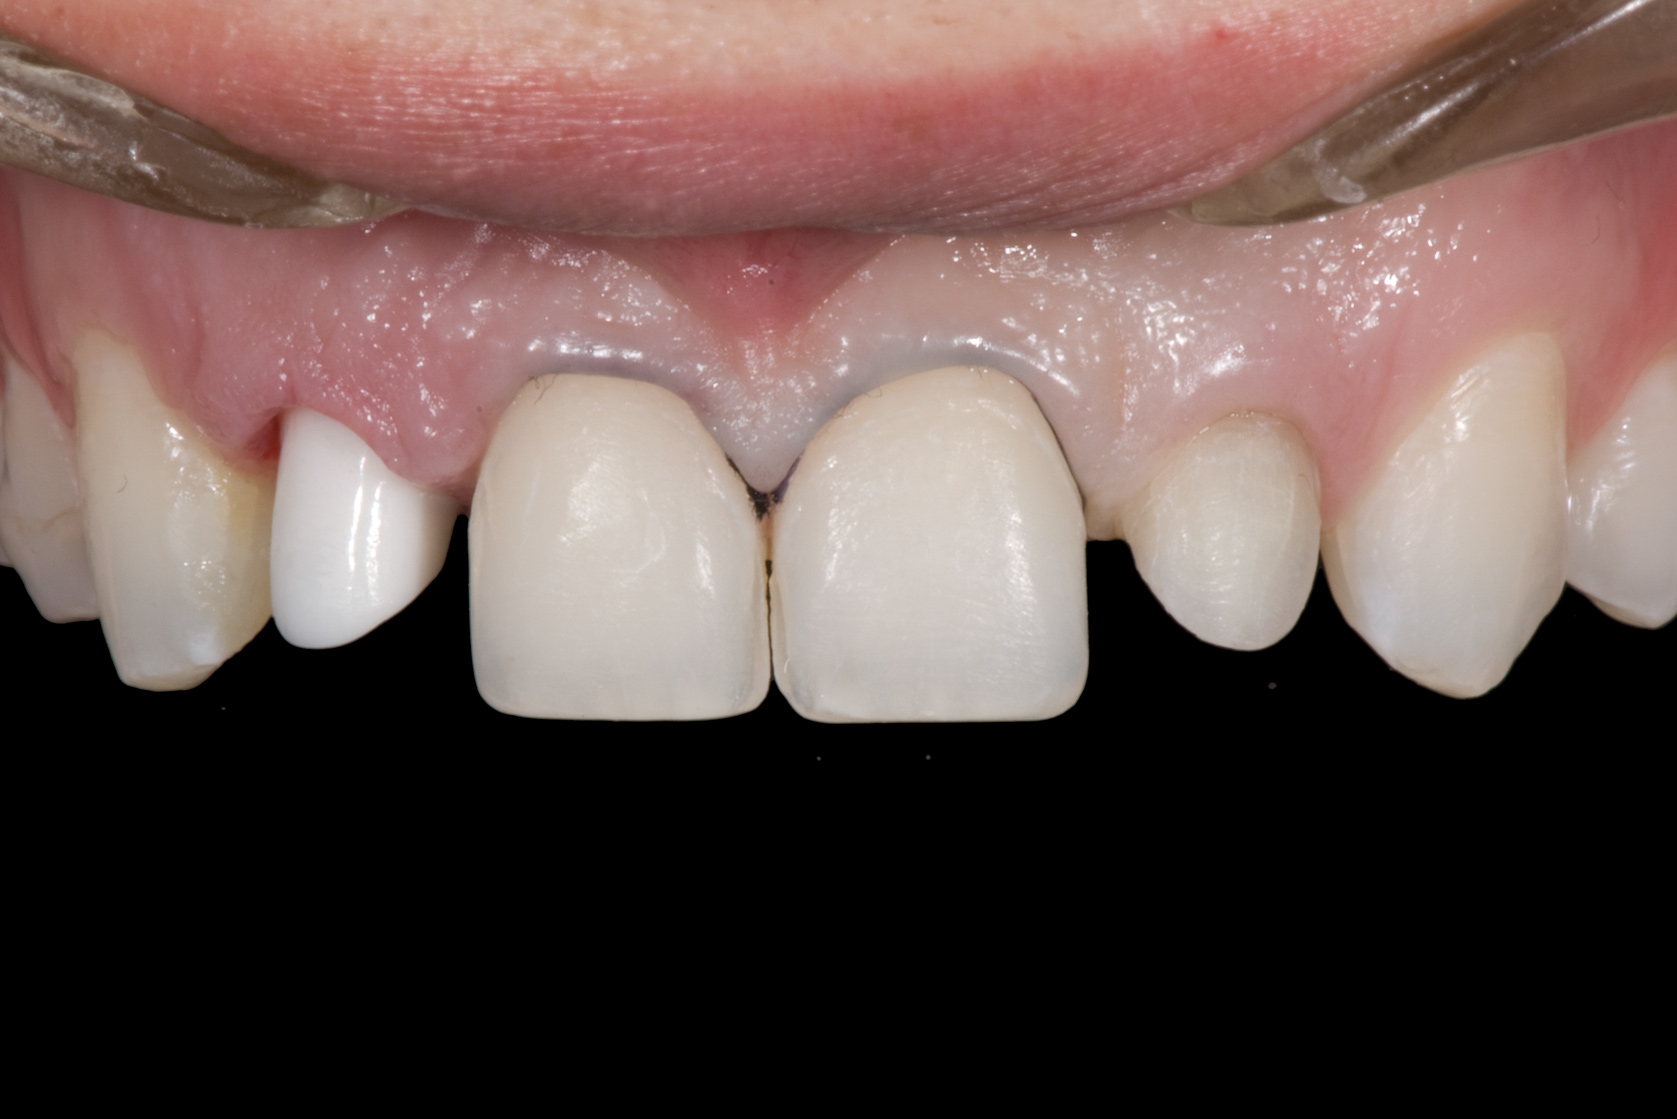

Fig 3. After resin-based composite bonding of the three incisors.

Figure 3

Once the teeth were bonded to ideal size, the "Maryland Bridge" was fabricated from a polyvinyl arch impression with the newly bonded teeth (Figure 3). The metal frame was cast from a non-precious alloy to allow for fabrication of a very thin frame and to create a better surface for bonding. After sandblasting the internal aspect of the frame with CoJet silica (3M ESPE), accomplishing salinization, and executing cementation with a dual-cure resin cement, a fairly good adhesion to the frame was anticipated.29 The enamel surface was etched with phosphoric acid for 30 seconds, the primer (Single Bond Plus, 3M ESPE) was applied to both the internal surface of the sandblasted framework and the etched enamel, and the bridge was cemented with RelyX ARC (3M Espe) dual-cured resin cement (Figure 4 and Figure 5).